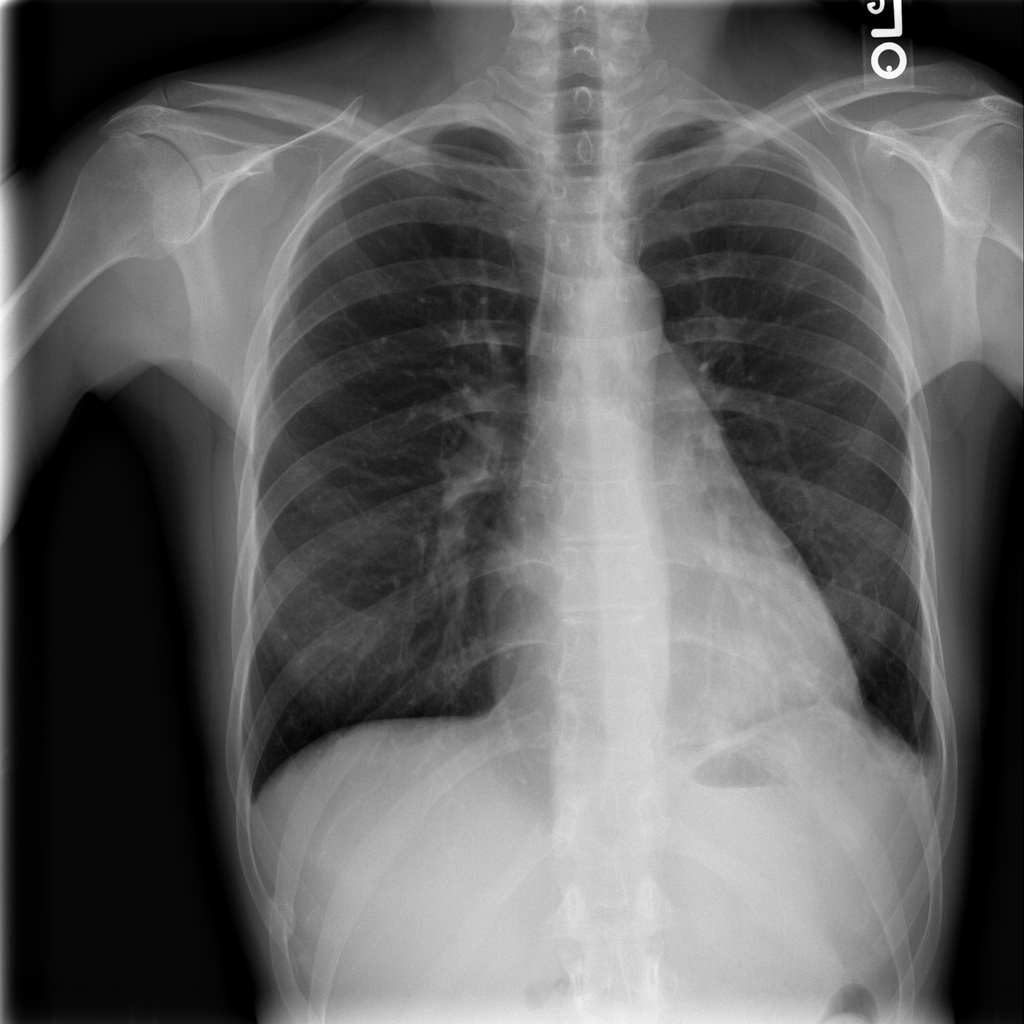

PAT-B3C3 · IMG-001Pneumonia

PAT-B3C3 · IMG-001

PA